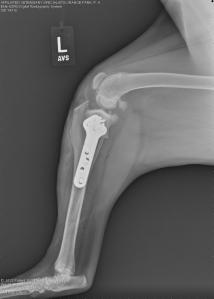

Right knee – note the joint swelling, arthritic changes, and forward movement of the tibia in relation to the femur.

Left knee – note the joint swelling, arthritic changes, and forward movement of the tibia in relation to the femur.